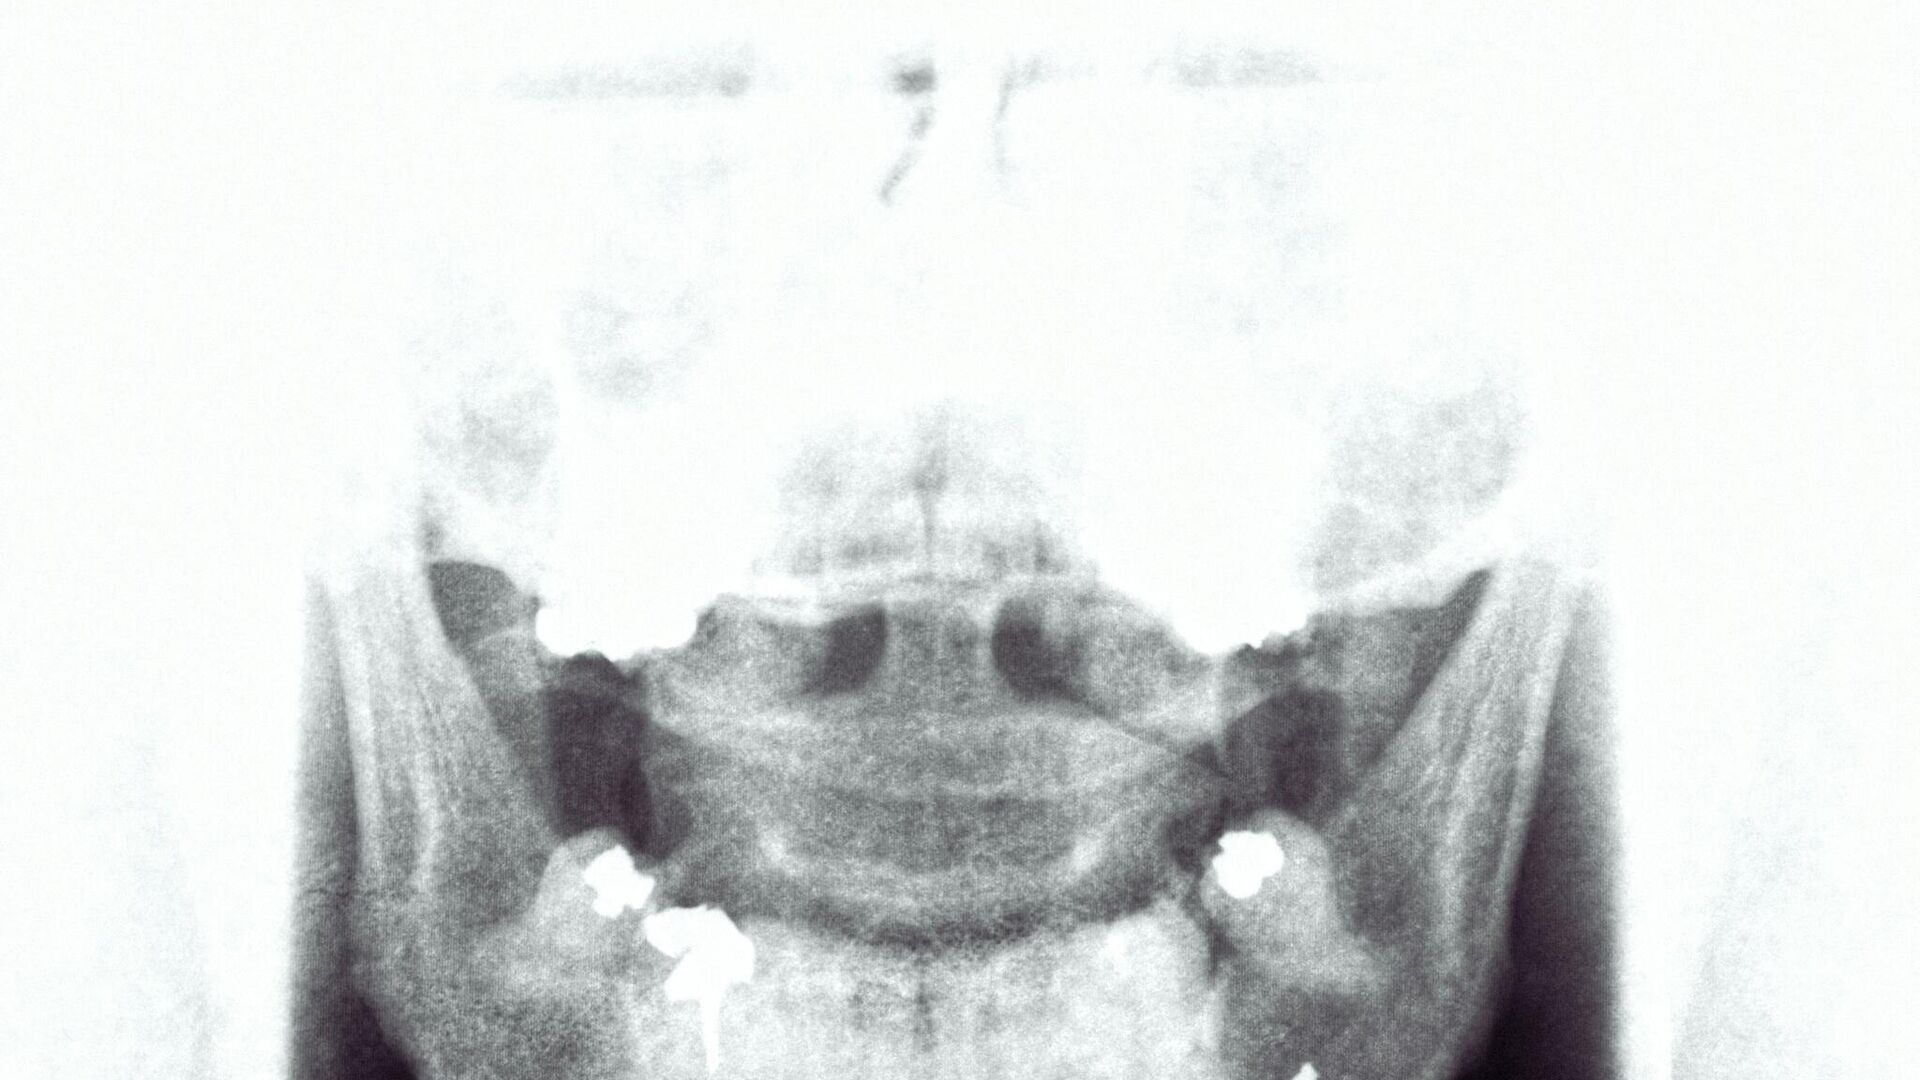

ويتم الحصول على صورة بالأشعة السينية على عدة مراحل: أولاً، يمر شعاع من الأشعة السينية عبر الجسم، ويمتص جزء منه بواسطة أوساط كثيفة، مثل أنسجة العظام، وفقا لما أوردته وكالة "سبوتنيك".

ويدخل الإشعاع المتبقي إلى "المستقبل" - الكاشف، وهو المادة التي يحولها (ما يسمى بالوامض) أولاً إلى إشارة ضوئية أخرى، ثم إلى إشارة كهربائية، ويتم الحصول على صورة رقمية منه، وفقًا للعلماء من جامعة سيبيريا الفيدرالية.